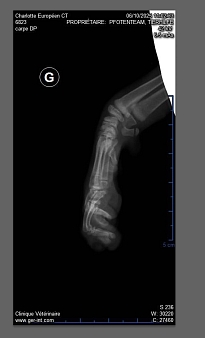

So  mussten beide einige Tage stationär in der Tierklinik an die Infusion, Charlotte hatte starkes Fieber, ihre Beine wurden geröntgt,  bei Dora hingegen setzte nach den Medikamenten eine Unterkühlung ein, sie musste auf die Wärmematte. Beide bekamen Antibiotika und es wurde ein Bluttest gemacht, die Ärztin vermutete einen akuten Calicivirusschub.